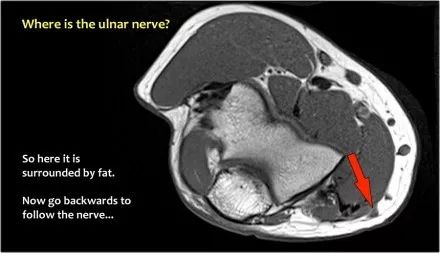

尺神经:在这里,我们看到了肘管内的尺神经。尺骨侧支带的后带形成隧道的底部,而支持带形成屋顶。

该患者有尺神经神经病变。肘管综合征是一种常见的周围神经病变。它产生于肘管内尺神经,其中该神经传递肘管支持带的下方的压缩。

因此,当我们回到图像时,您会发现很难找到神经。任何这些皮下结构都可以是转位神经。一种方法是远端跟随结构,直到你发现远端的尺神经位于由脂肪包围的前臂近端的正常位置。然后当你向近端跟随它时,你会发现这是皮下移位。